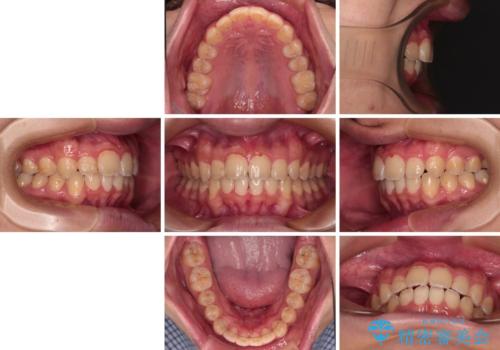

- 深く咬みこんだ前歯と、それに伴い前方に突出した上顎前歯を気にして来院された患者様です。

下顎の歯列は、奥歯が前方に傾斜し、前歯が上顎の歯の付け根に食い込むように内側に傾斜していました。

また、左右の犬歯の位置関係は上顎歯列が前方に位置する咬み合わせとなっており、インビザライン単体で治療するよりは、ワイヤー装置や補助装置を併用した方がより良い仕上がりになることが期待されました。

来院時は学生であったので、補助装置により上顎臼歯を後方に移動させ、下顎歯列はワイヤー装置による傾斜を改善させ、就職のタイミングでインビザラインにて仕上げていくこととしました。